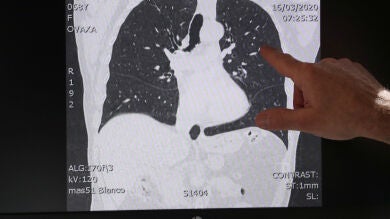

La imagen de cómo el coronavirus afecta a los pulmones de los pacientes más graves

El doctor Ignace Demeyer trabaja en un hospital de Flandes, en Bélgica, y está atendiendo a afectados por el coronavirus. Ha mostrado una serie de imágenes de escáner donde se aprecia la diferencia entre pulmones sanos y pulmones dañados por el COVID-19.

En las imágenes se muestran los efectos de la neumonía que provoca este nuevo coronavirus y que se ha convertido en la peor consecuencia de la infección. Para el 80% de la población la enfermedad cursa con síntomas leves pero hay quien tienen que ser ingresado o, en un menor porcentaje, pasar por una Unidad de Cuidados Intensivos.

El médico asegura que algunas de estas imágenes "dan miedo" y ha decidido mostrar a la opinión pública estos ejemplos para que sean conscientes de que es importante seguir las medidas adoptadas por las autoridades sanitarias.